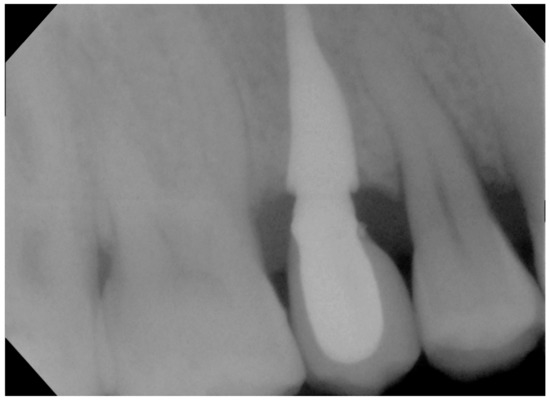

3. Results